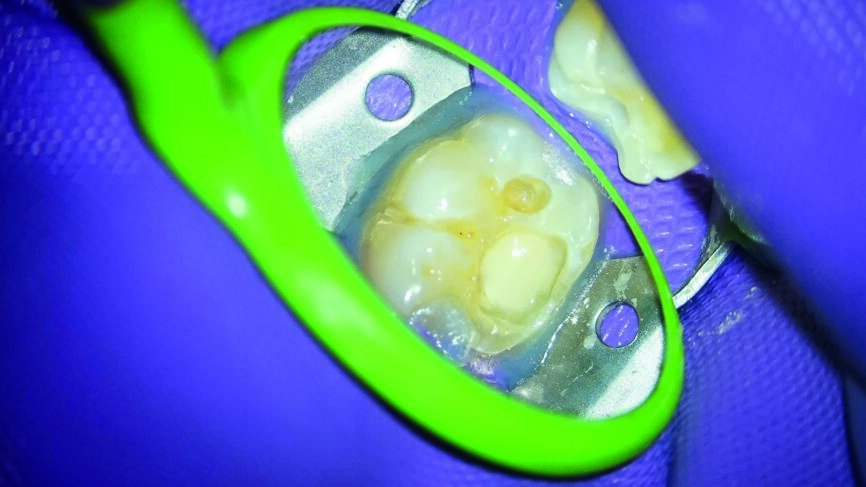

Ein 24-jähriger Patient kam mit vorübergehenden, provozierten Zahnschmerzen an Zahn #19 in die Zahnklinik (Abb. 1). Die Diagnose lautete reversible Pulpitis. Die Zahnfäule wurde unter kompletter Isolation entfernt, wobei es zweimal zur Freilegung der Pulpa mit minimalen Blutungen kam (Abb. 2). Die Blutungen wurden gestoppt, indem 10 Sekunden lang ein mit steriler Salzlösung getränkter Wattebausch auf die Stelle gedrückt wurde. Die Mundhöhle wurde mit 2,5% Natriumhypochlorit desinfiziert (Abb. 3), anschliessend wurde weißes MTA (Produits Dentaires) als Mittel zur unmittelbaren Pulpa-Überkappung eingesetzt (Abb. 4). Um sicherzustellen, dass das MTA korrekt eingesetzt wurde, kam das MAP-System für Dentalmaterialien (Produits Dentaires) zur Anwendung. Mit diesem System kann der Klinikarzt das Material exakt an der Expositionsstelle anbringen. Somit wird eine Verunreinigung der Dentinwände verhindert, die mit der Zeit eine Pigmentierung infolge des verwendeten Materials aufweisen könnten (Abb. 5 und 6). Sobald das MTA auf die Expositionsstellen der Pulpa und die tieferliegenden Teile des Pulpakammerdachs aufgetragen wurde, kam eine lichthärtende Kalziumhydroxidpaste zum Einsatz, um das Material zu schützen (Abb. 7), das Klebeverfahren durchführen und die abschliessende Zahnreparatur in derselben Sitzung vornehmen zu können (Abb. 8 und 9). Sieben Tage nach dem Verfahren war der Patient komplett symptomfrei und der Zahn reagierte normal auf Sensitivitätstests. In solchen klinischen Situationen ist davon auszugehen, dass zwischen sechs und neun Monaten nach dem Verfahren die Bildung von Kalkgewebe unter dem Überkappungsmaterial in Röntgenaufnahmen nachgewiesen werden kann. (7)